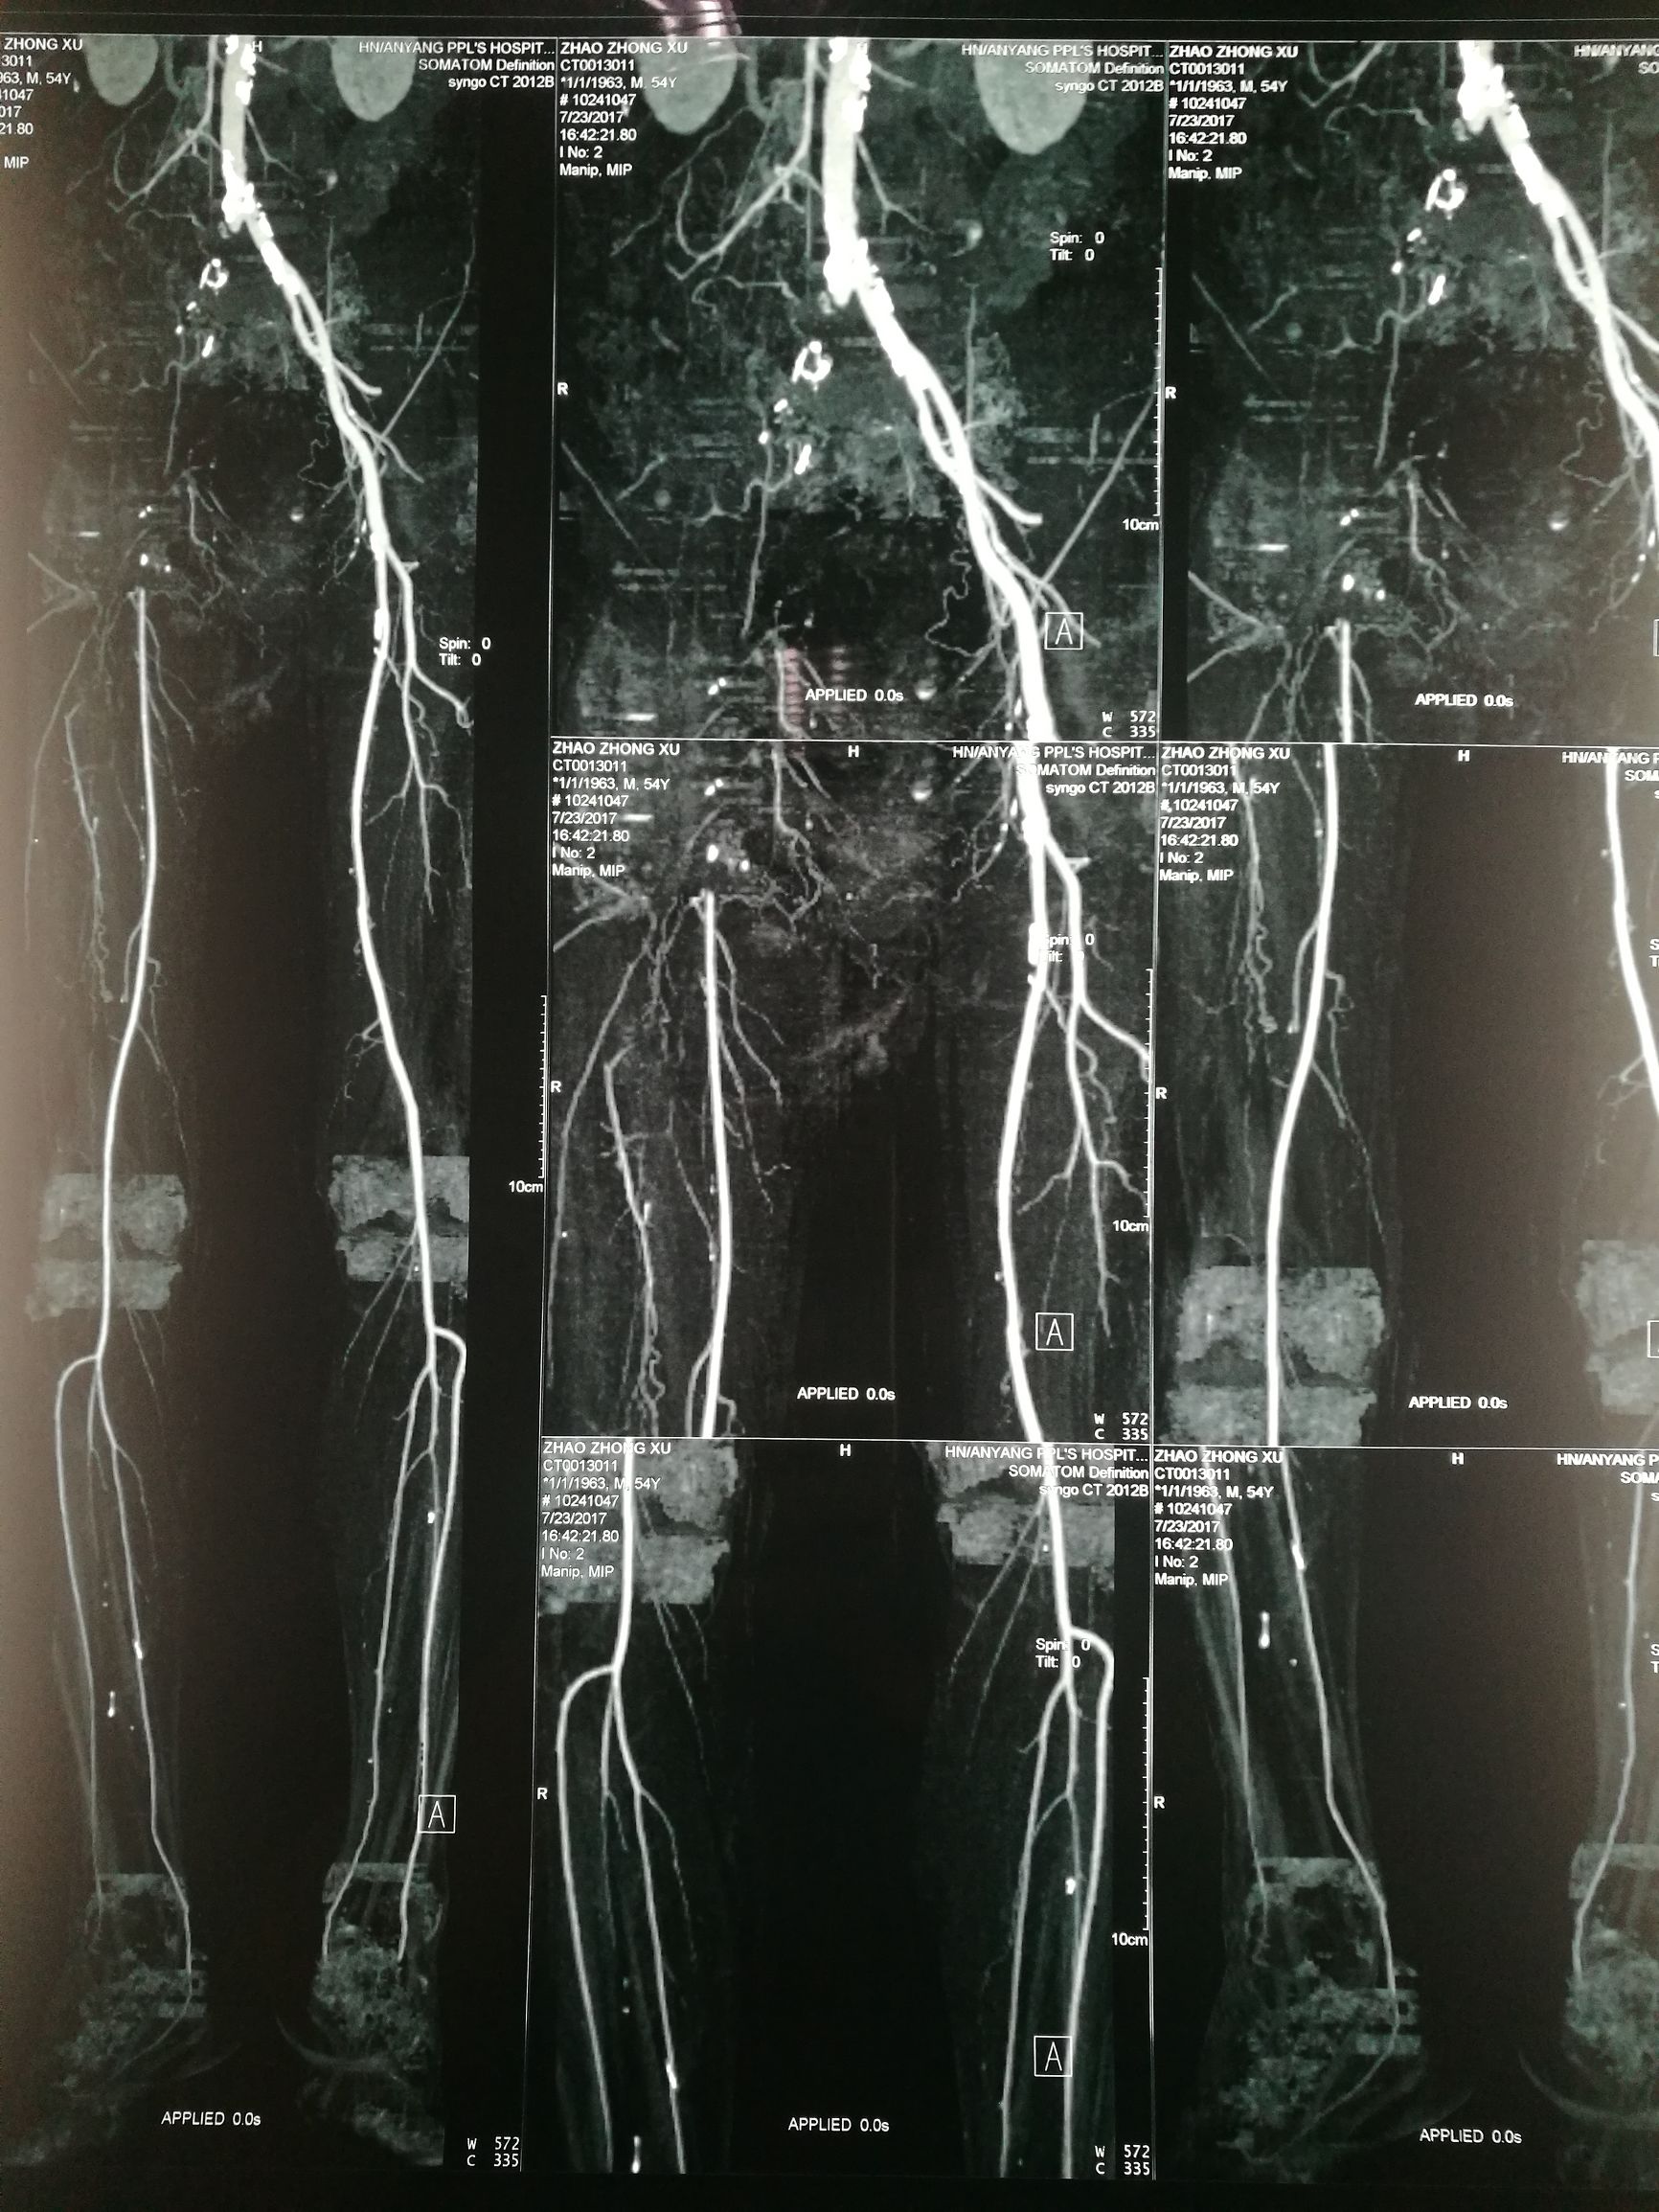

对比正常解剖模式图,我们可以发现:右侧髂总髂内髂外股总动脉未显影,股深动脉未显影,右侧股浅动脉起始段未见显影,考虑有血栓闭塞的可能。

术前经讨论,考虑股深动脉的重要性,决定开刀取栓基础上对残余狭窄介入治疗。

患者平卧位,常规消毒铺单,局麻下切开显露右侧股总动脉和股深动脉、股浅动脉。全身肝素化后,切开股动脉,对股浅动脉取栓后远侧回血好,对股深动脉反复取栓后出现汹涌回血。近端取栓后用导丝导管通过闭塞段到达腹主动脉下段,造影证实在真腔,用5*80mm球囊扩张后造影,髂动脉内有部分充盈缺损。植入巴德Fluency8*100和8*60覆膜支架后用7*60球囊扩张,造影管腔光滑(如图)。缝合动脉切口,关闭伤口,术毕。